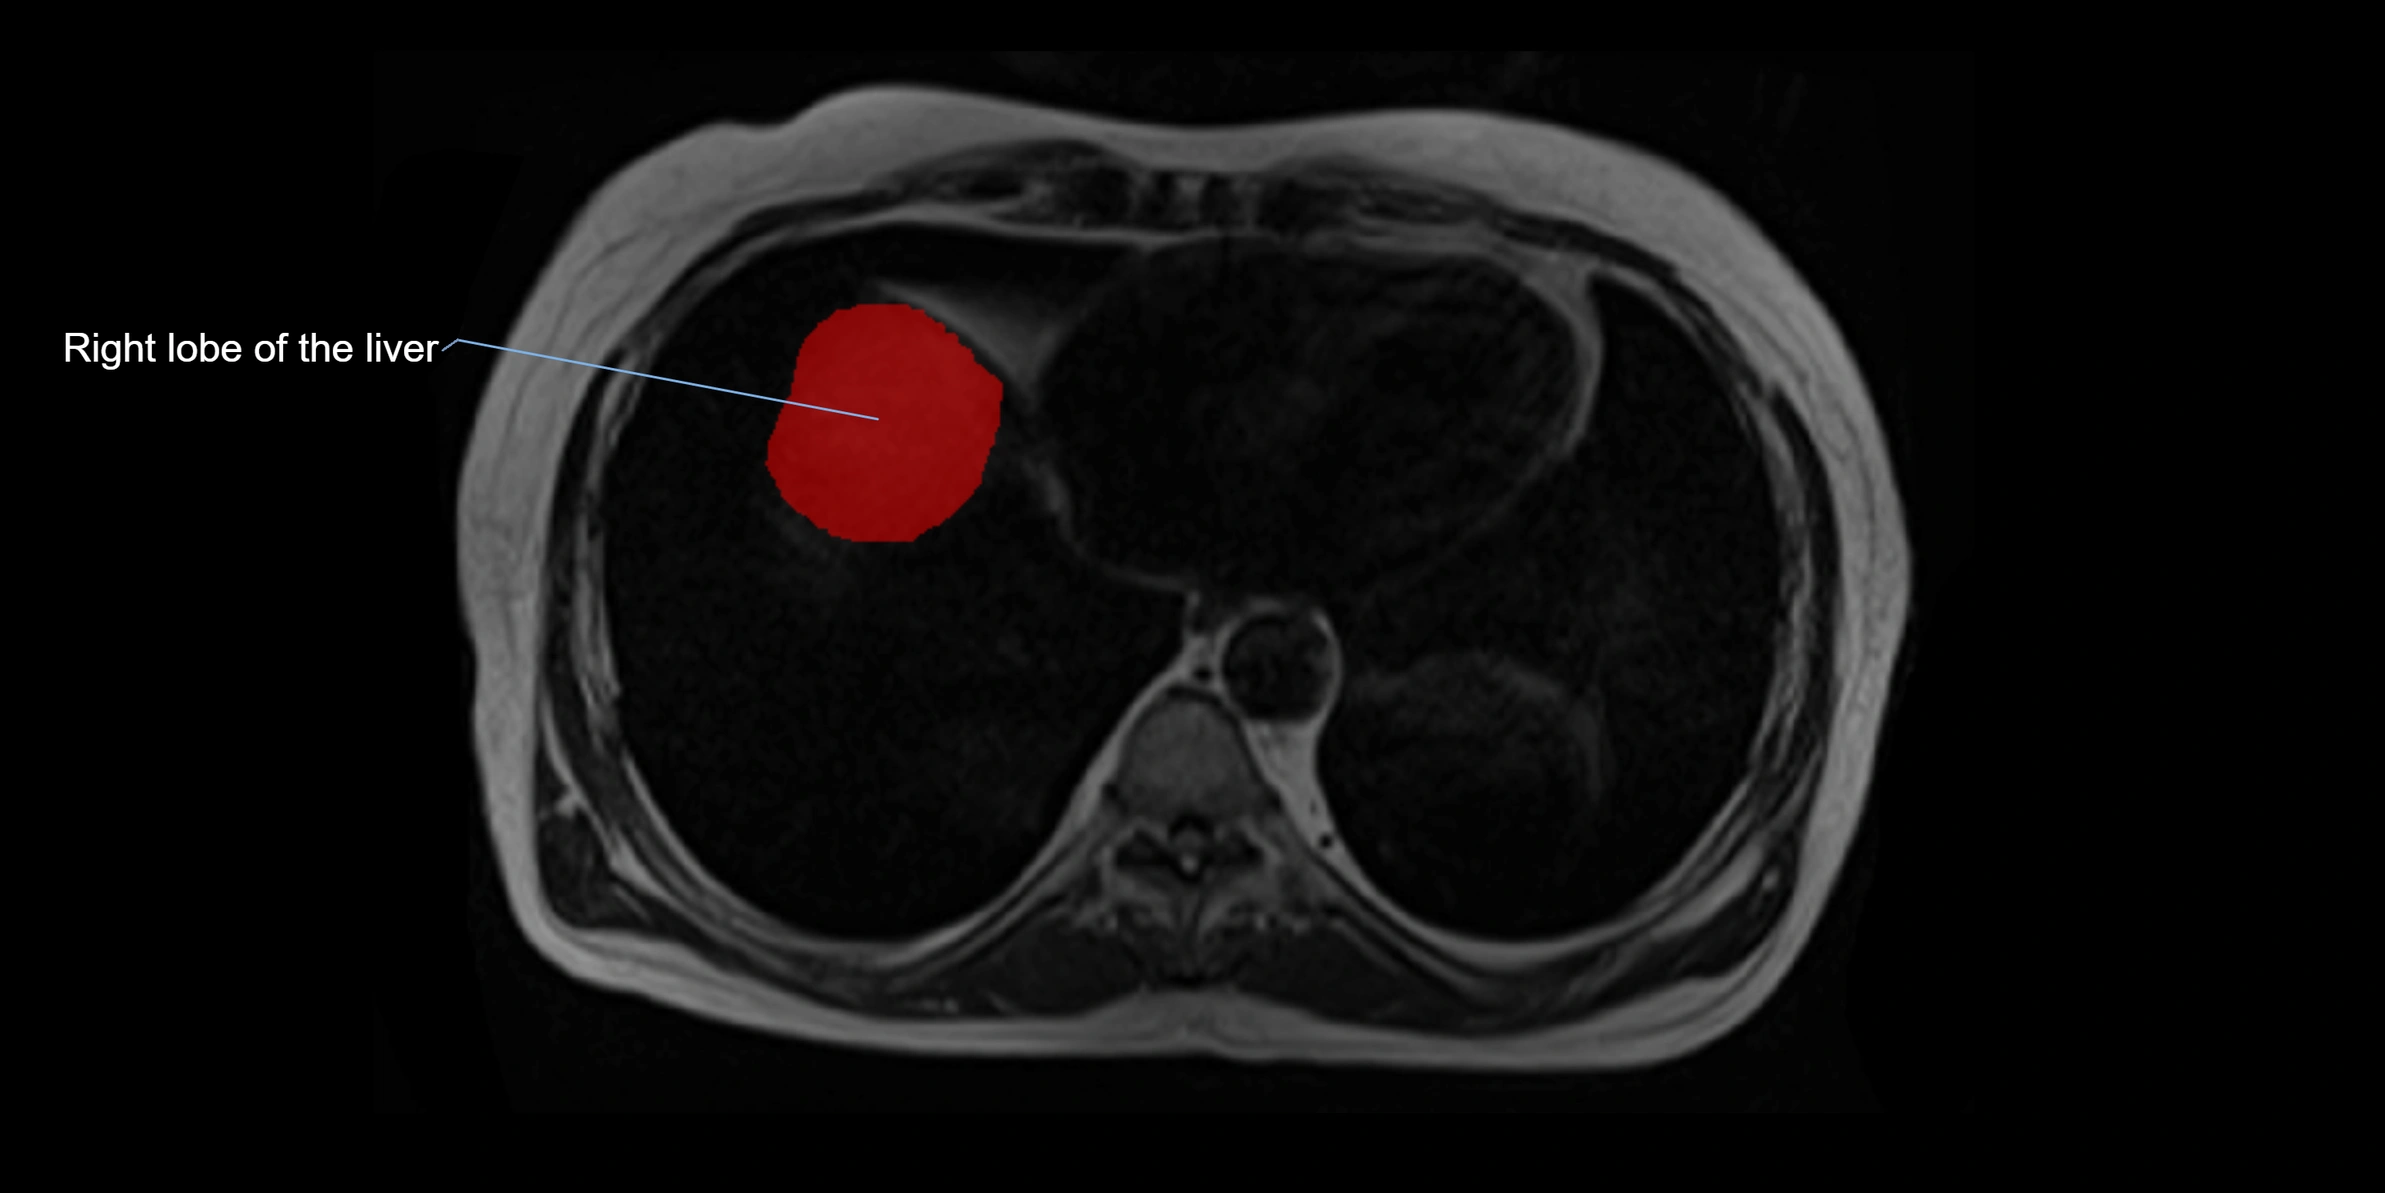

The caudate lobe of the liver is a distinct anatomical subdivision of the liver, designated as segment I in Couinaud’s classification. It lies on the posterior surface of the liver, between the fissure for the ligamentum venosum (left boundary) and the groove for the inferior vena cava (IVC) (right boundary). Superiorly, it is related to the posterior liver surface, and inferiorly it is separated from the left lobe by the porta hepatis.

MRI image